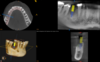

Cas n°4: Elévation Sinusienne Crestale par la technique de Summers

Il s’agit d’une intervention Stérile réalisée sous Anesthésie Locale d’une quarantaine de minutes lorsque la hauteur osseuse résiduelle entre le sinus et la cavité buccale est comprise entre 5 et 8mm. L’objectif est de repositionner la membrane sinusienne (Schneider) au dessus de l’apex de l’implant. Le temps de cicatrisation est de 4mois, il faudra respecter le cahier des charges à savoir durant 8semaines post-opératoires : pas de plongée sous-marine, pas d’avion, ne pas se pincer le nez lors d’un éternuement ou encore pas de sport avec essoufflement intense.